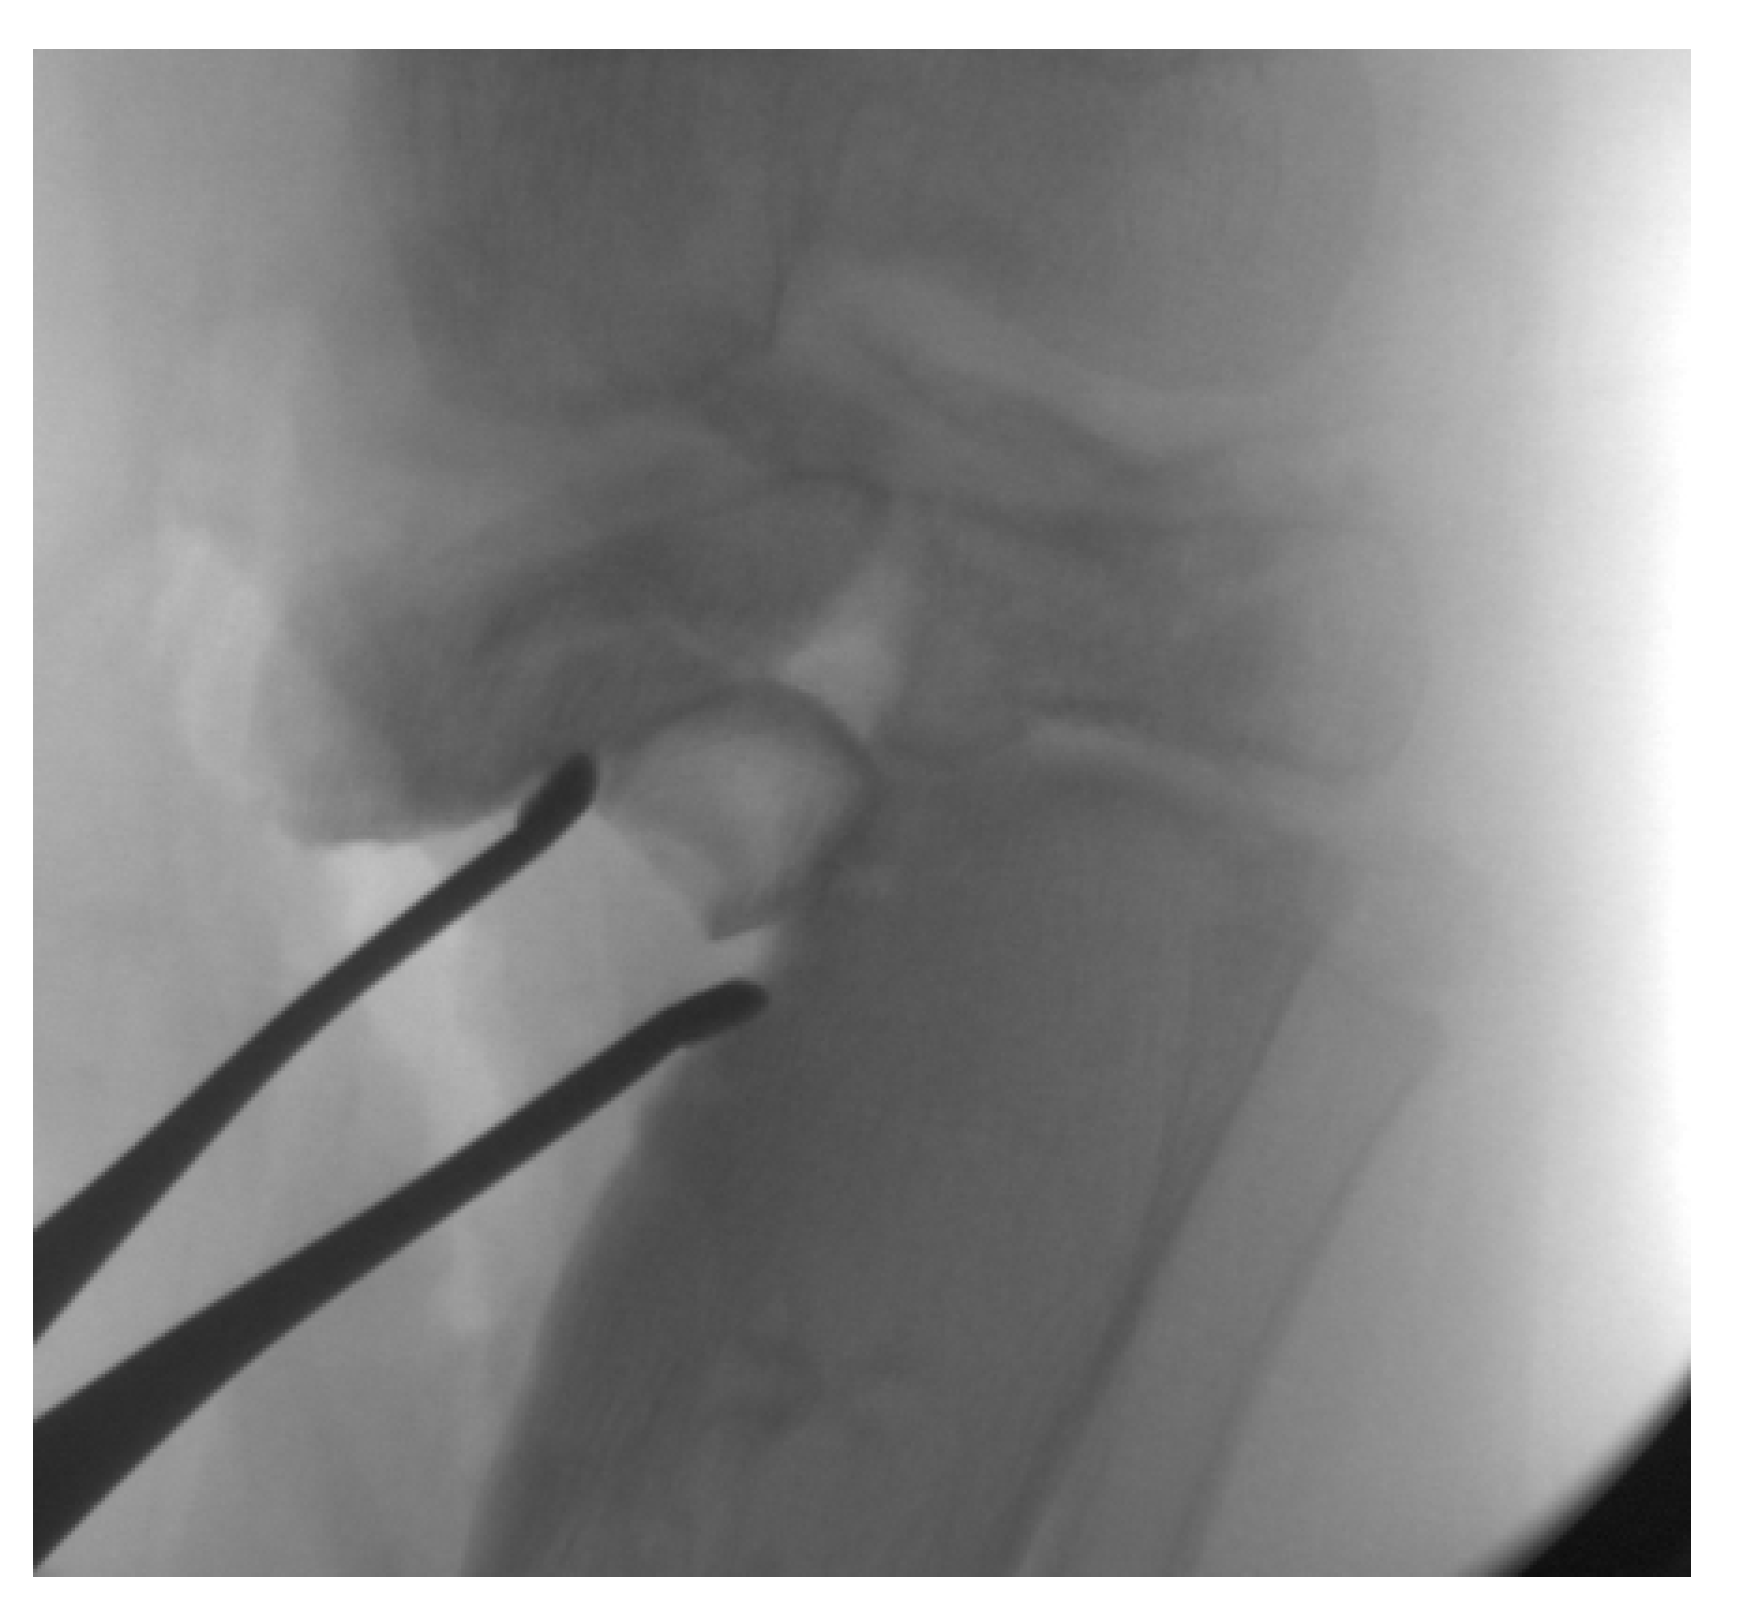

13. Osteotomies with Acute Correction

14. Hemi-Plateau Elevation Osteotomy